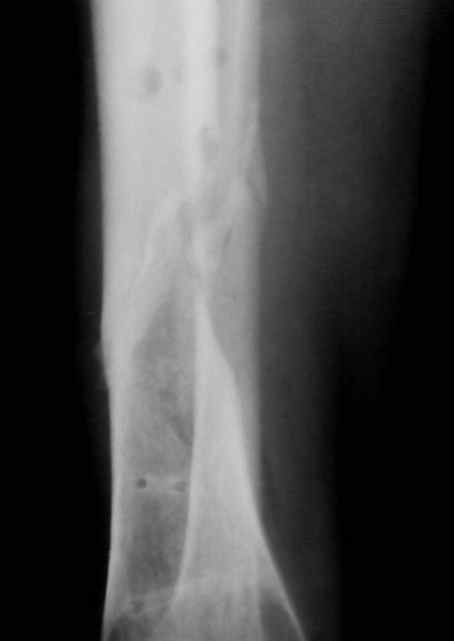

Больная 54 года, 5 м. назад открытый оскольчатый перелом 2-3 тип, Первично ЧКДО, открытое ведение раны, при этапных некрэктомия " ушел" осколок внутренней стенки б/бецовой кости, 7 сутки пластика м/тканями ,вторичные швы.

Контакт отломков только по спирали наружной стенки,заживление раны полное, на 3-4 месяце ЧКДО воздействие на регенерацию микродистрациями , 5 месяц снят аппарат по причине нестабильности и реакции м/тканей. В данный момент проблем с тканями нет, на Р-граммах псевдоартроз, клинически подвижность,больная ходит в ортезе с дозированной нагрузкой.Местно рубцовый процесс 3х5 в зоне перелома.

Будьте добры послать снимки до операции . а также после операции, на которых видна компановка аппарата Илизарова. Кстати на представвленных рентгенограммах в аппарате есть спица с напайкой, проведённая проксимально перелома через обе кости... Если можно, объясните необходимость такого проведения.

"Кстати на представвленных рентгенограммах в аппарате есть спица с напайкой, проведённая проксимально перелома через обе кости..."

Там две спицы с напайкой дистально и проксимально и обе только через 1 кость

Встречно-боковая компрессия по классике, удержать отломки от смещения по ширине

Уже сделали -кровь спокойная,при радионуклиидном исследовании(технеций)накопление в с-н/3 + 80% Иключили или доказали ? Не знаю, исходим из того, что она спит.